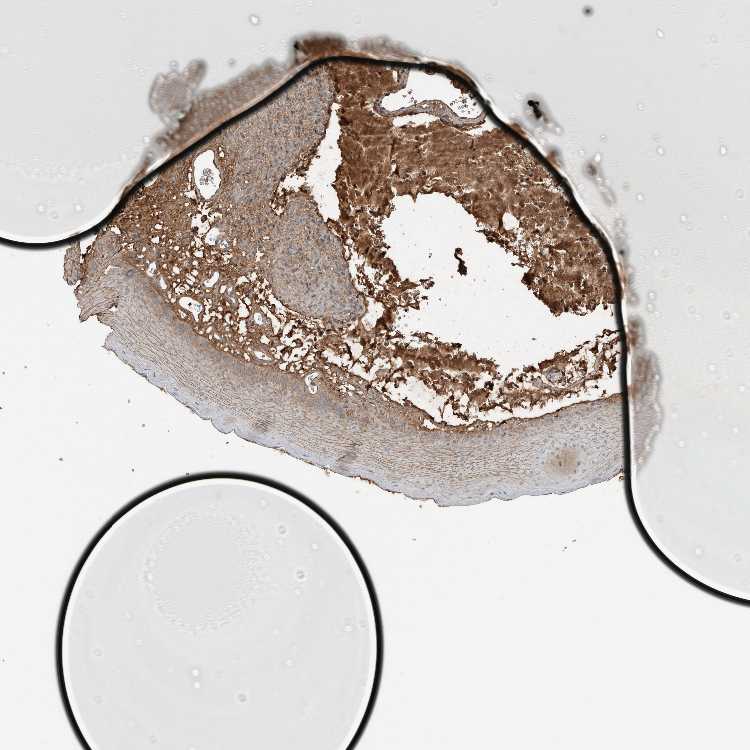

ORAL MUCOSA - Antibody stainingi

Antibody staining in the annotated cell types in the current human tissue is reported as not detected, low, medium, or high, based on conventional immunohistochemistry profiling in selected tissues. This score is based on the combination of the staining intensity and fraction of stained cells.

Each image is clickable and will lead to virtual microscopy that enables deeper exploration of all samples and also displays staining intensity scores, fraction scores and subcellular localization as well as patient and tissue information for each sample.

Antibody HPA025815

Squamous epithelial cells Medium